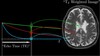

What is this graph showing?

The free induction decay curve